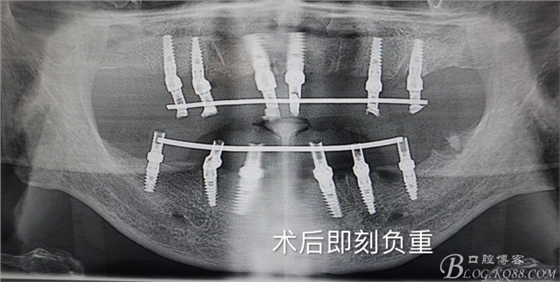

四塊導板.全口種植.即刻負重